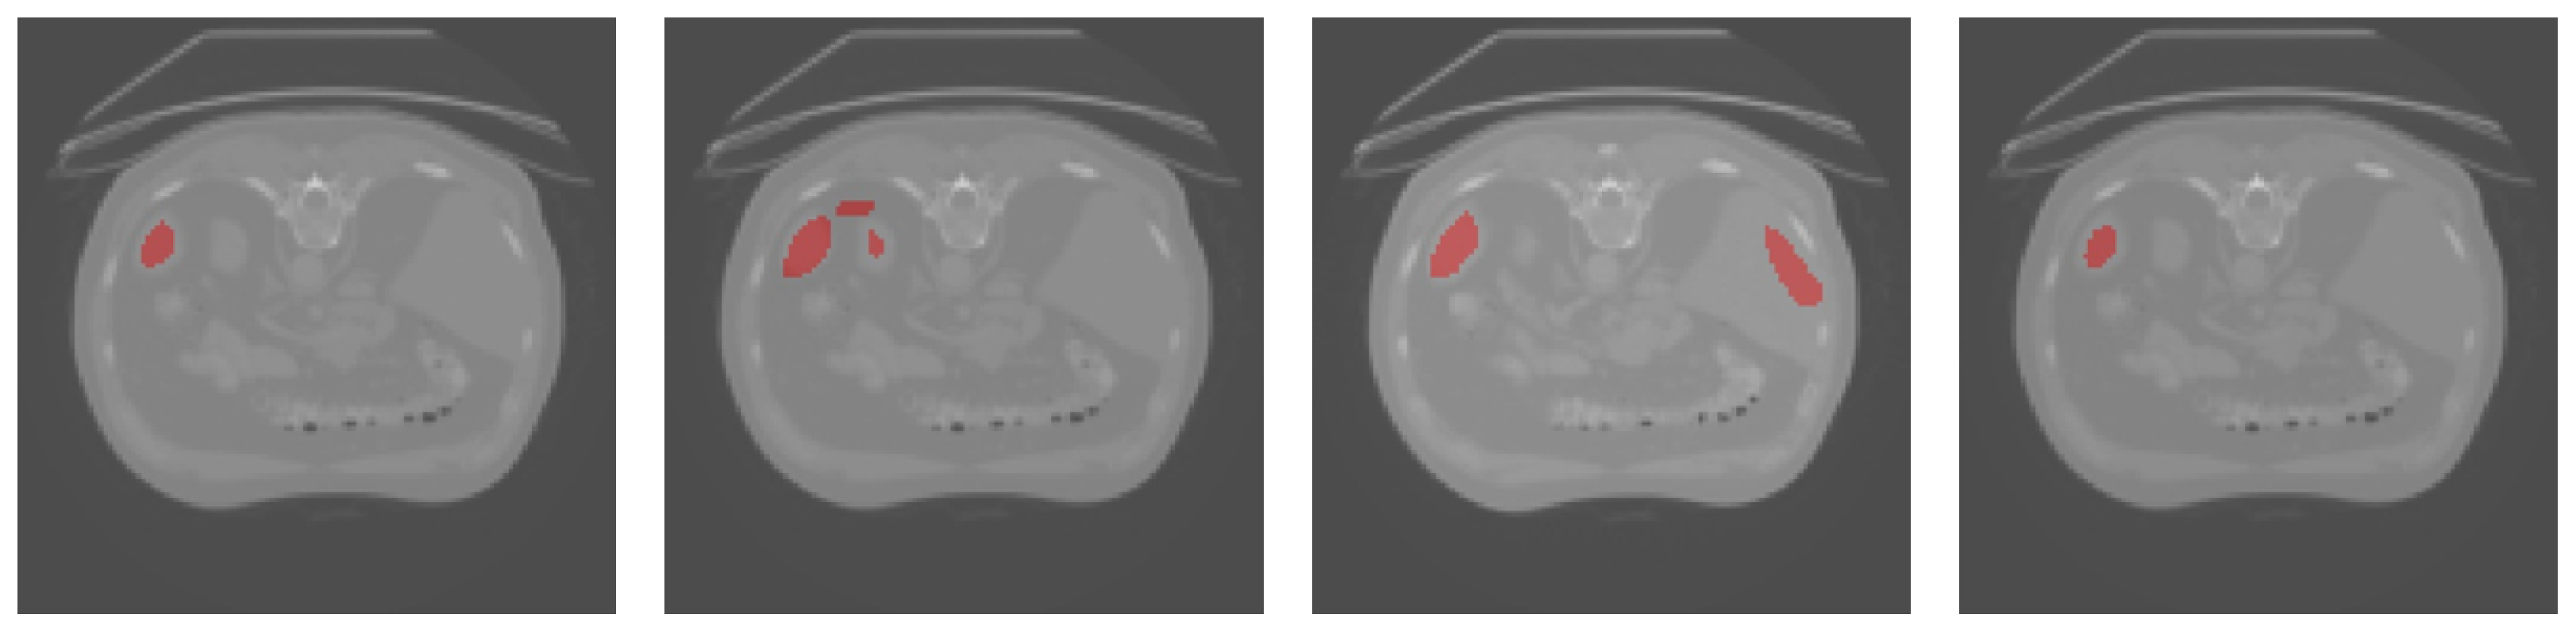

3.3. Results Obtained on the Spleen and Liver CT Datasets

| Dice | TPR | TNR | HD95 | |

|---|---|---|---|---|

| U-Net | 42.36% | 27.46% | 99.99% | 5.60 |

| UNet++ | 50.36% | 37.14% | 99.96% | 5.00 |

| Att-UNet | 53.15% | 50.20% | 99.88% | 7.00 |

| Focus-UNet | 35.19% | 27.42% | 99.91% | 14.46 |

| SAB-Net | 57.32% | 58.40% | 99.89% | 5.10 |

| U-Net | 55.88% | 42.11% | 99.15% | 8.77 |

| UNet++ | 58.78% | 46.28% | 98.90% | 8.00 |

| Att-UNet | 60.16% | 50.82% | 98.21% | 6.40 |

| Focus-UNet | 46.10% | 38.36% | 97.24% | 8.06 |

| SAB-Net | 61.13% | 50.27% | 98.60% | 7.07 |